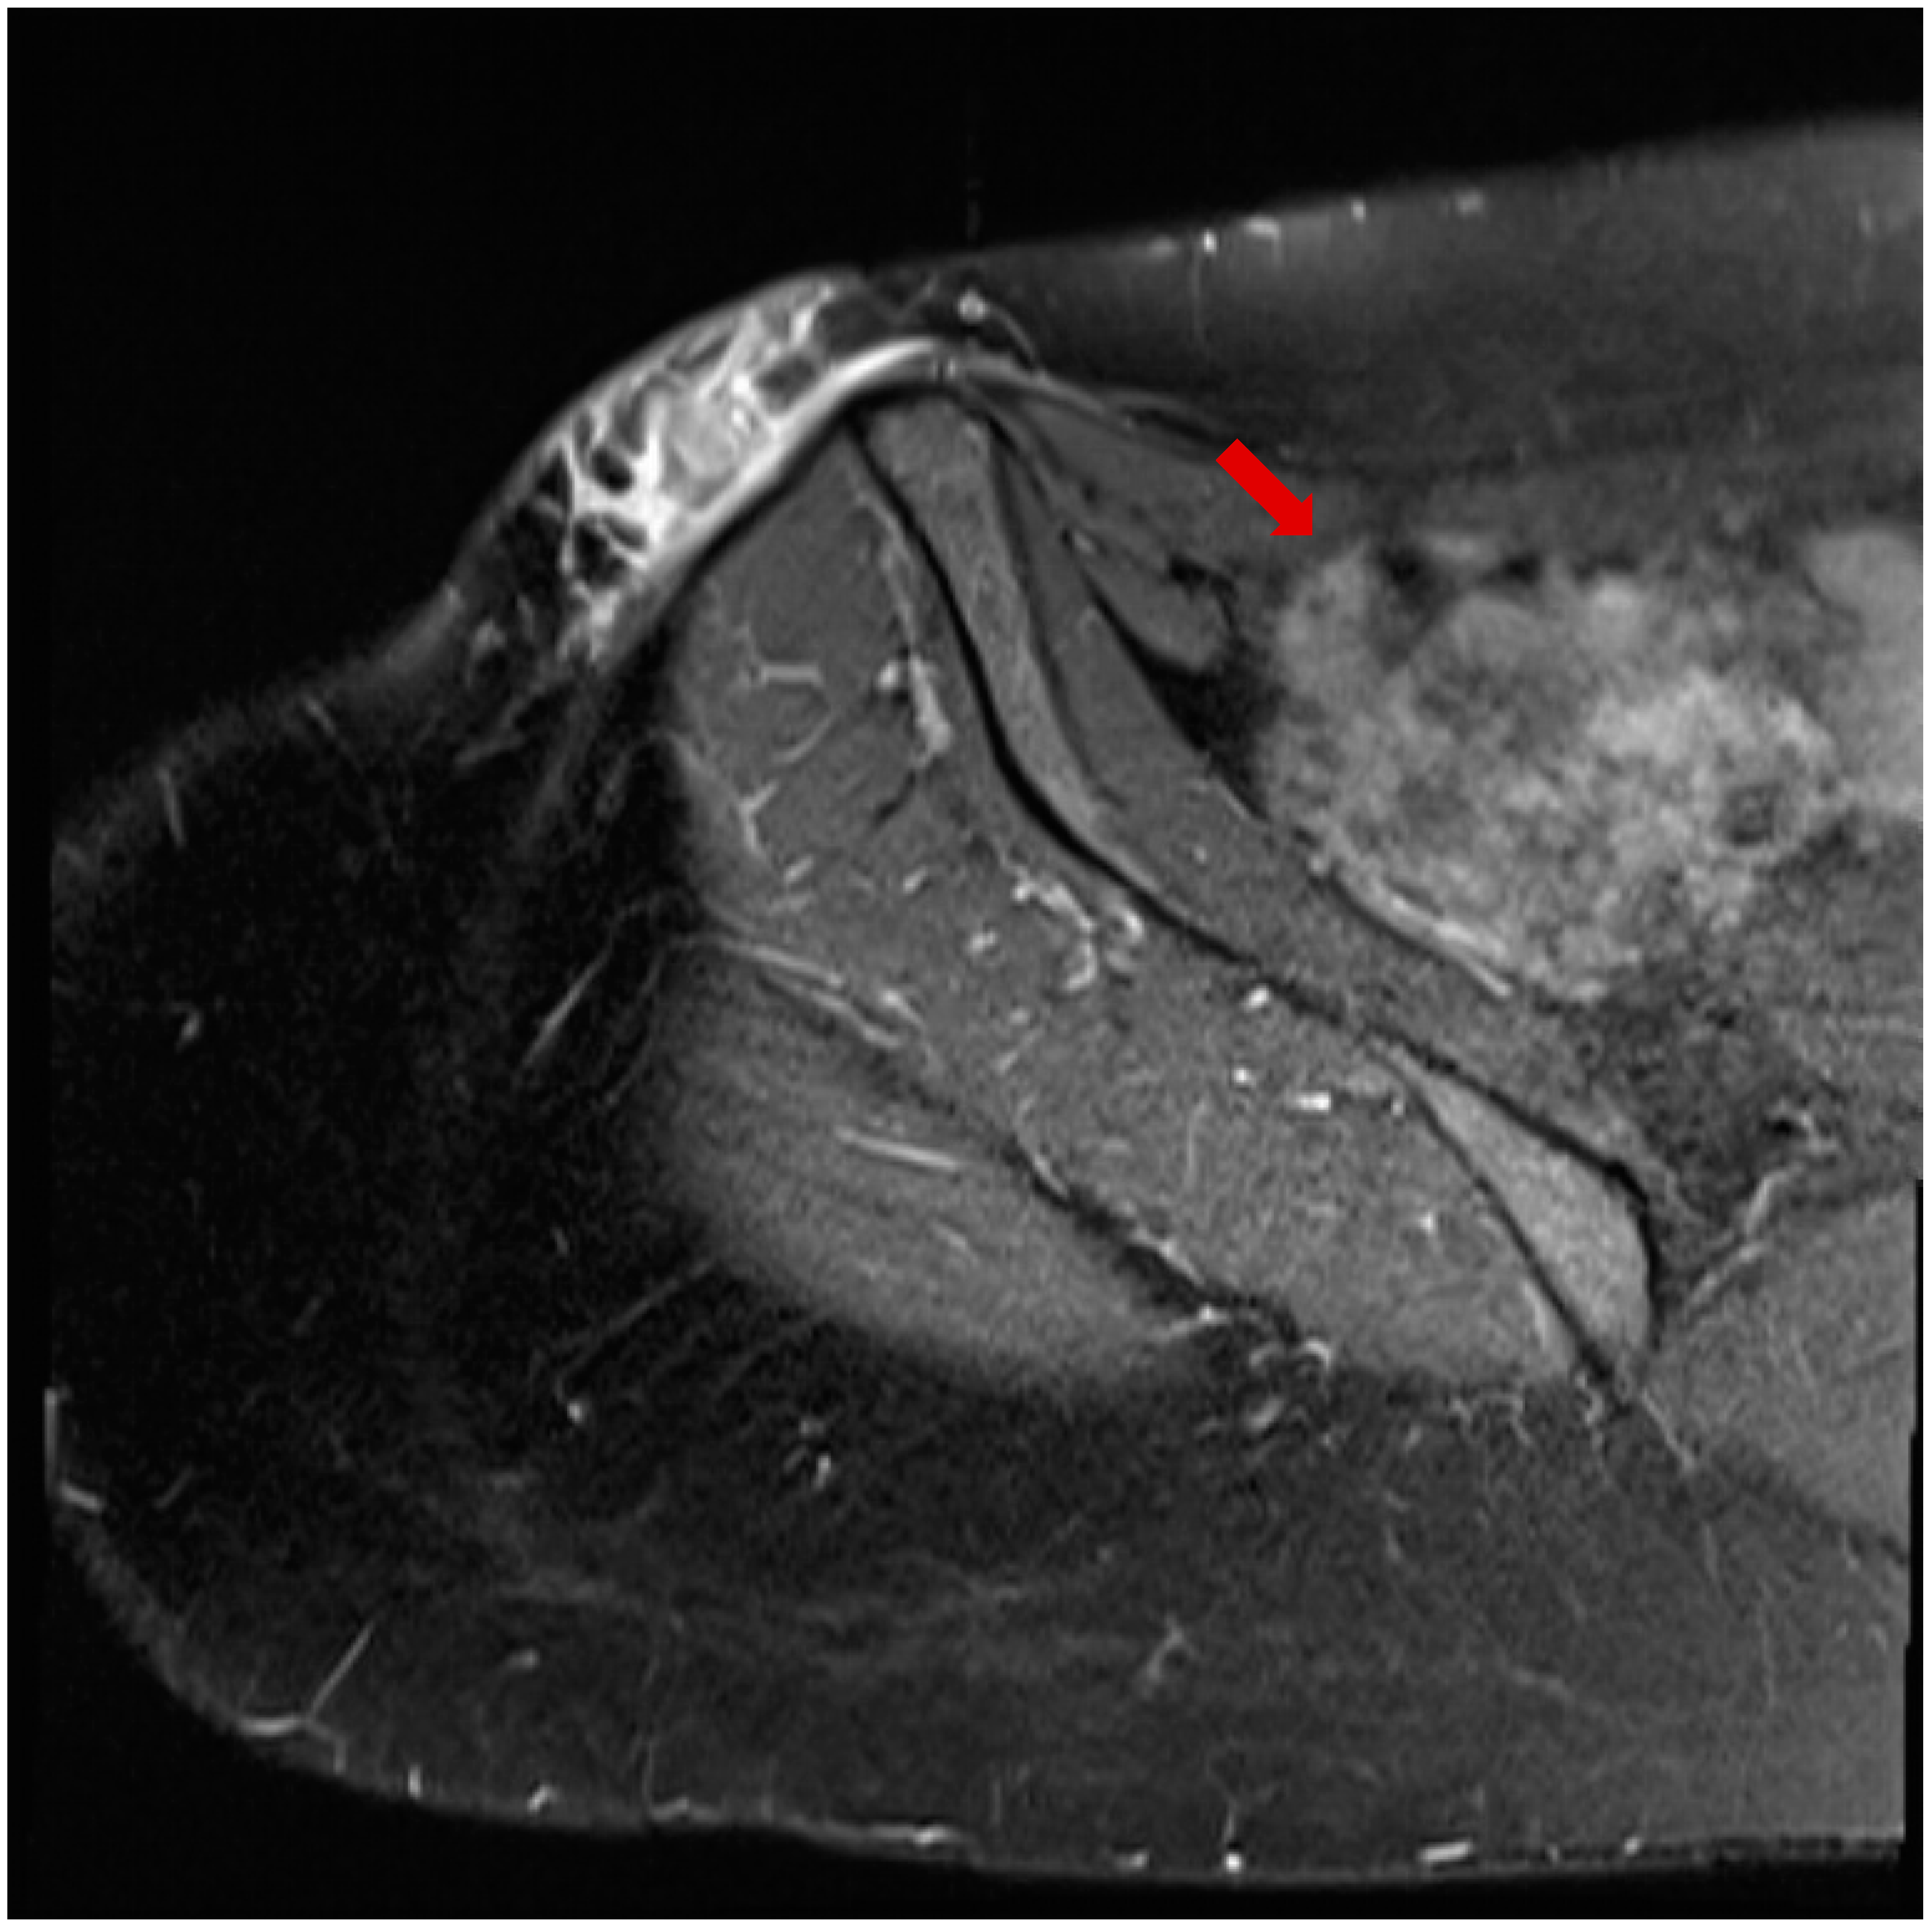

The patient, a 41-year-old female, presented to the infectious diseases outpatient clinic in June 2024 after noticing a swelling in the left groin area that had progressed in size. The first symptoms appeared in April 2024. Initially, the swelling resembled a mosquito bite and did not attract the patient’s attention. But the subcutaneous nodule persisted and began to grow steadily over the course of 8 weeks. During the anamnesis, the patient stated that she often traveled to Kefalonia in Greece. Her last trip before the medical clarification and excision was in August 2023. Symptoms were relatively mild and limited to mild itching at the site of the swelling. The patient reported no systemic symptoms and stated that she was in good physical condition. There were no relevant prior diseases, except a mild iron deficiency syndrome. The complete blood count was unremarkable, but the differential blood count revealed a slight eosinophilia (407 cells/µL and 9.2%, respectively). Three consecutive stool analyses for parasites were negative. Ultrasound examination revealed the swelling to be an encapsulated, easily displaceable mass measuring 3.9 cm in length, 2.6 cm in width, and 1.5 cm in depth. The mass was partially filled with fluid. The MRI confirmed the result of the sonographic examination, with the growing mass being diagnosed as an unclear tumor (Figure 1). It was decided to surgically remove the mass in June 2024 and to send the resected tissue to a pathology laboratory for further examination. On macroscopic examination, the tumor presented as a nodular, beige-colored mass with a lipomatous character. The resected subcutaneous adipose tissue presented with panniculitis and focal abscess formation. There was a clear histiocytic demarcation from the tumor mass, which had a chitin-like character and a cystic configuration (Figure 2). The resected tissue did not stain with Grocott methenamine silver, Alzian blue, or Giemsa. Only Periodic acid-Schiff (PAS) staining showed a delicate colorability of the tumor material. In sum, the histopathological examination results strongly suggested a parasitic infestation. Formalin-fixed paraffin-embedded tumor material was transferred to the parasitology lab at the Medical University of Vienna for further clarification. Based on the sections, the symptoms, and the travel history, the presumptive diagnosis dirofilariasis was made, which was proven by a polymerase chain reaction (PCR) specific for D. repens [15] after DNA extraction from the fixed material. The patient was completely free of symptoms after removal of the mass, with simultaneous regression of eosinophilia, thus no antiparasitic therapy was initiated. Abdominal ultrasonography and exploratory echocardiography performed in September 2024 during a follow-up examination of the patient were unremarkable, so there was no evidence of organ involvement.

Figure 1.

MRT image of the swelling in the left groin showing a mass measuring 3.9 cm in length, 2.6 cm in width, and 1.5 cm in depth (arrow).